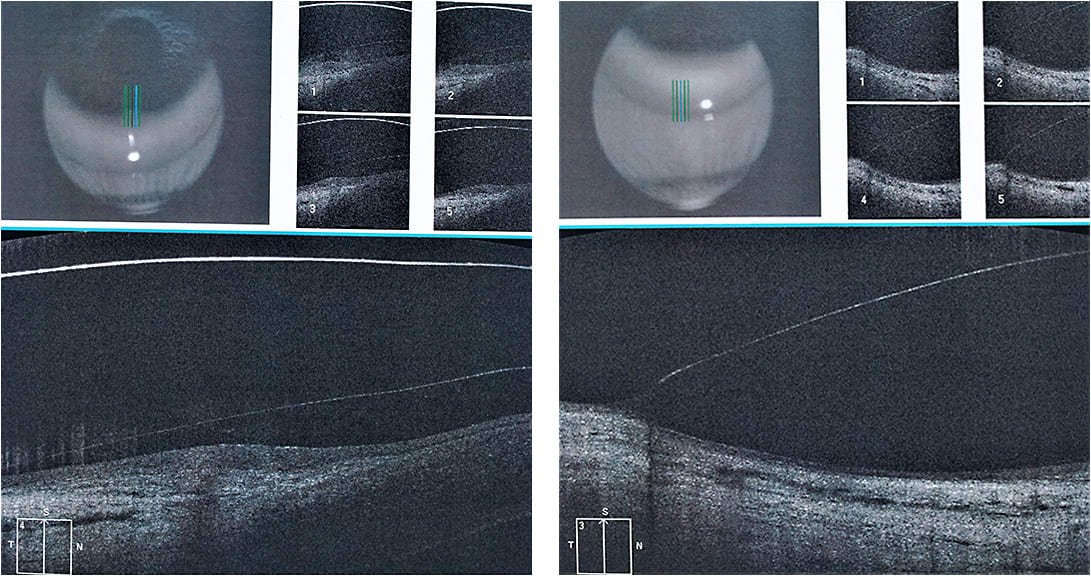

With fluorescein, we also observed superior touch at the limbus and areas in which the haptic was loose (Figures 3 and 4). The loose and the tight areas were also evident in optical coherence tomography (OCT) images. Despite this, the patient did not complain of discomfort.

The 15.7mm scleral lens worked very well, especially with the modifications; the sag was ideal, and there was no touch at the limbus despite the really short landing zone due to a small haptic. This lens also centered better (Figure 5) compared to the 17.5mm and 16.5mm lenses.

To maintain the desired vault over the cornea, we changed the base curve and secondary base curve to obtain the best possible alignment (Figure 6).

The anterior cornea OCT images were of great help to better estimate the necessary changes to the scleral lens designs (Figures 7 through 10). We started using this method a few years ago, but we use it only when necessary. Most of our scleral lens fits do not require OCT, as the scleral lens design that we typically fit has a slightly flatter haptic alignment horizontally compared to the vertical haptic.